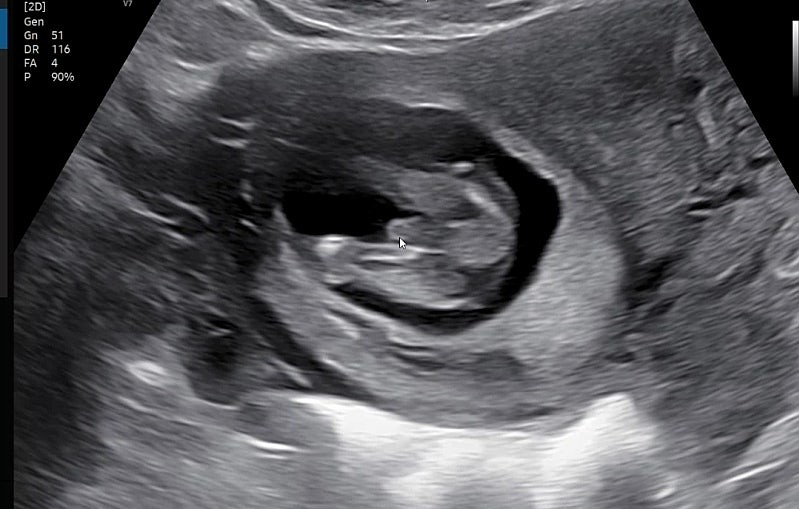

14주차 초음파보고 왔는데...빼박 🌶 인가용..?

ㅎㅎ 아들맘 확정인가요?

너무 아들이네여ㅎㅎㅎ